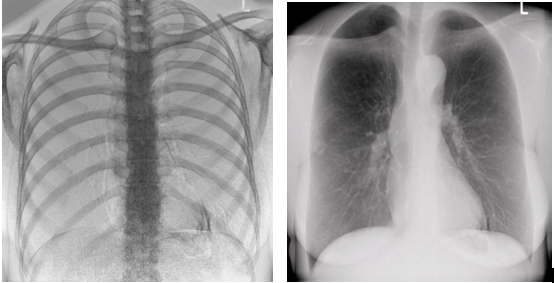

3)高帧速

最高帧速可达30帧/秒,获得与静态采集相媲美的高清流畅影像;

采用先进的脉冲透视技术,呈现更优图像空间分辨率、低对比度分辨率、灰阶范围,为精准诊断提供可靠依据。

4)透视+高清点片

在可视过程或回放过程中,如发现疑似病灶,可进行毫秒级高清点片,随时抓取单帧图像,精准捕抓病灶,便于医生进一步诊断分析,减少误诊,并有助于快速编制报告。